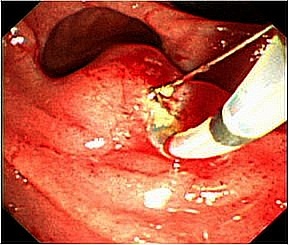

総胆管結石に対する低侵襲な内視鏡治療

胆石は胆嚢、胆管内につくられた結石のことをいい、胆管に作られた結石を総胆管結石

と呼びます。総胆管結石に対してはまず内視鏡によって胆管の出口を拡張して結石を摘

出する内視鏡的乳頭切開術(EST)を行います。胆管の出口を広げた後、結石除去用の

バスケット鉗子を胆管内に挿入して結石を除去します。ほとんどの場合は内視鏡治療で

胆管結石を除去することが可能ですが、内視鏡治療が困難と判断した場合は手術(腹腔

鏡下胆管結石切開結石除去術)で摘出します。また状況に応じて(高度な急性胆管炎を起こ

している場合)胆道ドレナージを行います。

胆管結石症に対する内視鏡治療の実際

治療手技はまず十二指腸まで挿入した内視鏡から胆管内にカテーテルを挿入し、造影剤

を注入し胆管および膵管の観察をします(内視鏡的逆行性胆管膵管造影(ERCP))。

胆管の形状や胆管内の結石を確認します。続いて総胆管結石の除去に移ります。胆管の

出口(十二指腸乳頭部)を広げるために乳頭切開を行います(内視鏡的乳頭切開術

(EST))。出口を広げた後、結石除去用のバスケット鉗子を胆管内に挿入して結石を除去

します。